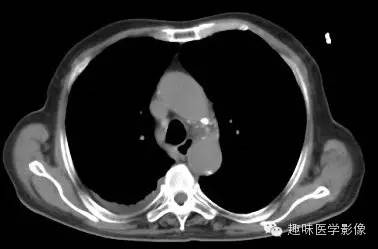

【病例】肺脓肿1例CT影像特点

男,71岁,发热待查。

双肺多发无壁低密度区,以右肺下叶底部为主。右肺下叶见大片不规则实变阴影伴多发空洞影,实变肺组织内见支气管气象,右肺下叶支气管局部显示不清。纵隔内见淋巴结。右侧胸腔内见积液影,邻近胸膜肥厚。主动脉、冠状动脉钙化。

右肺下叶肺脓肿、肺炎伴胸腔积液,肺气肿、肺大泡。

右胸廓变小,心影右移;右肺下叶多房性空洞,空洞内未见明显液平面,右下肺病变应该是下叶阻塞性肺炎,实变肺组织内见支气管气像,邻近胸膜增厚,并合并胸腔积液,支持肺脓肿。